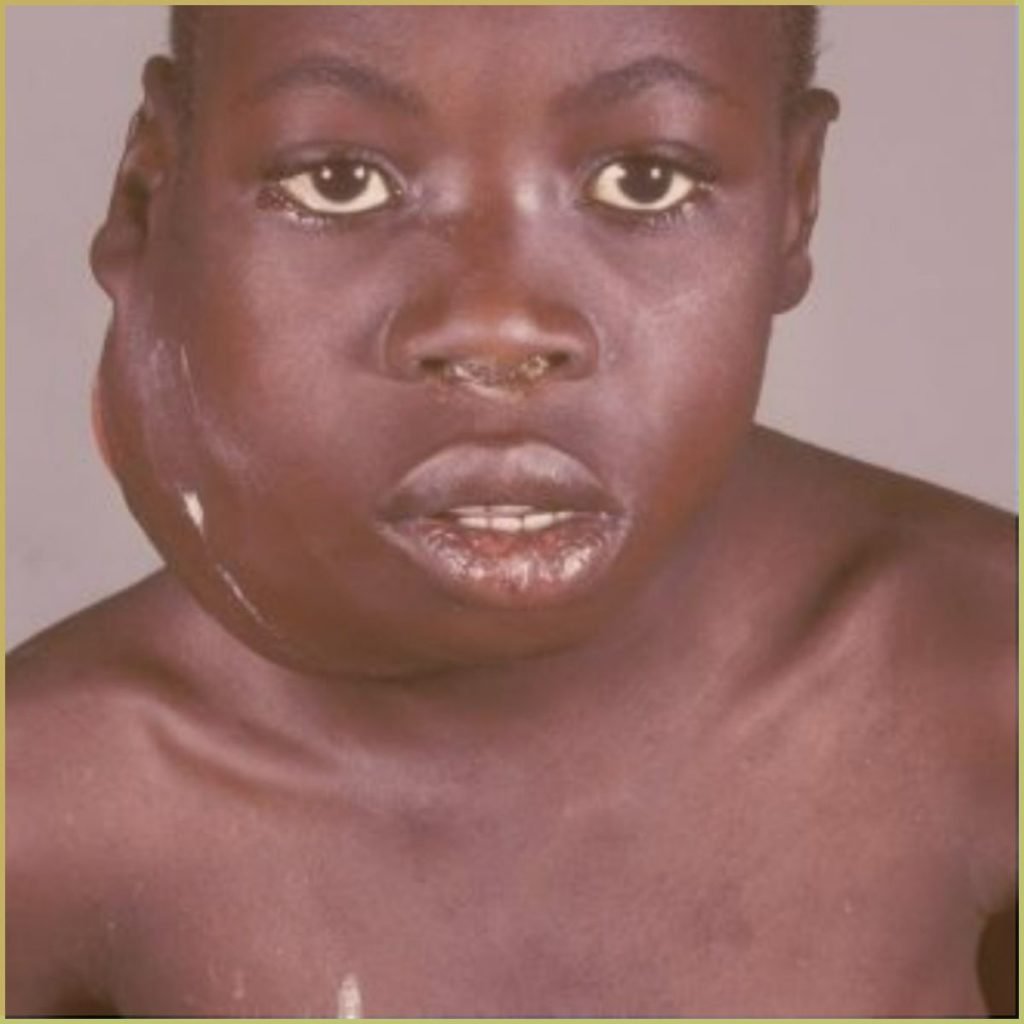

BURKITT LYMPHOMA

Burkitt Lymphoma (BL) is a highly aggressive B cell non-Hodgkin lymphoma associated with various genetic mutations (C-MYC, P53, TCF transcription factor) and exposure to certain pathogens (Epstein-Barr virus, Malaria). The endemic variant (African variant) most commonly affects the facial bones of children in malaria-endemic regions. The sporadic variant (non-African variant) is rarely associated with the Eptein-Barr virus and is more strongly associated with the abdominal (retroperitoneal) region. The common clinical presentation includes:

- Rapidly progressive facial tumor causing asymmetry.

- Quick dissemination to extranodal sites including CNS and bone marrow.

- Mainly affects the mandible (especially endemic variant).

- Proptosis, pain and paresthesia.